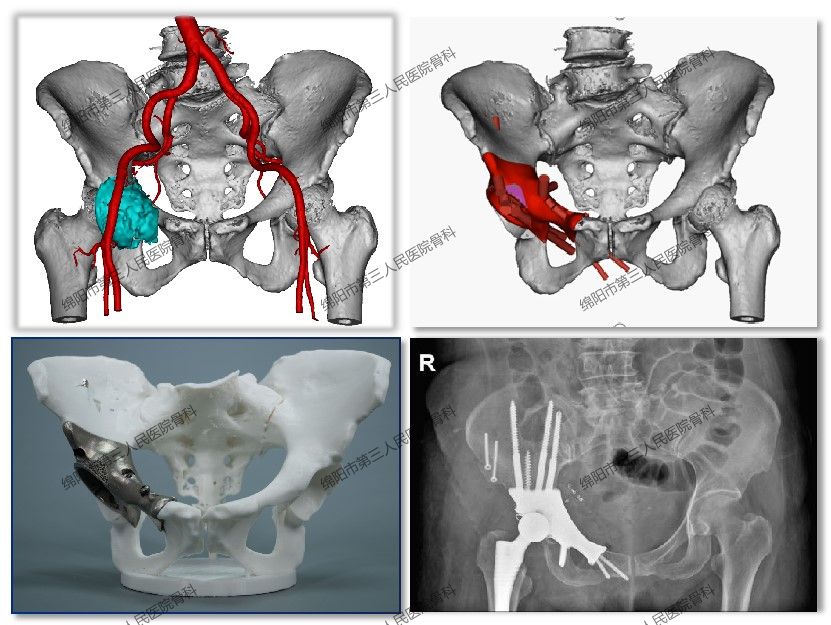

• 3D打印私人定制“骨骼”,本地骨肿瘤患者足不出市

3D打印私人定制“骨骼”,本地骨肿瘤患者足不出市 2023-05-10 作者 | 骨科/刘利娟